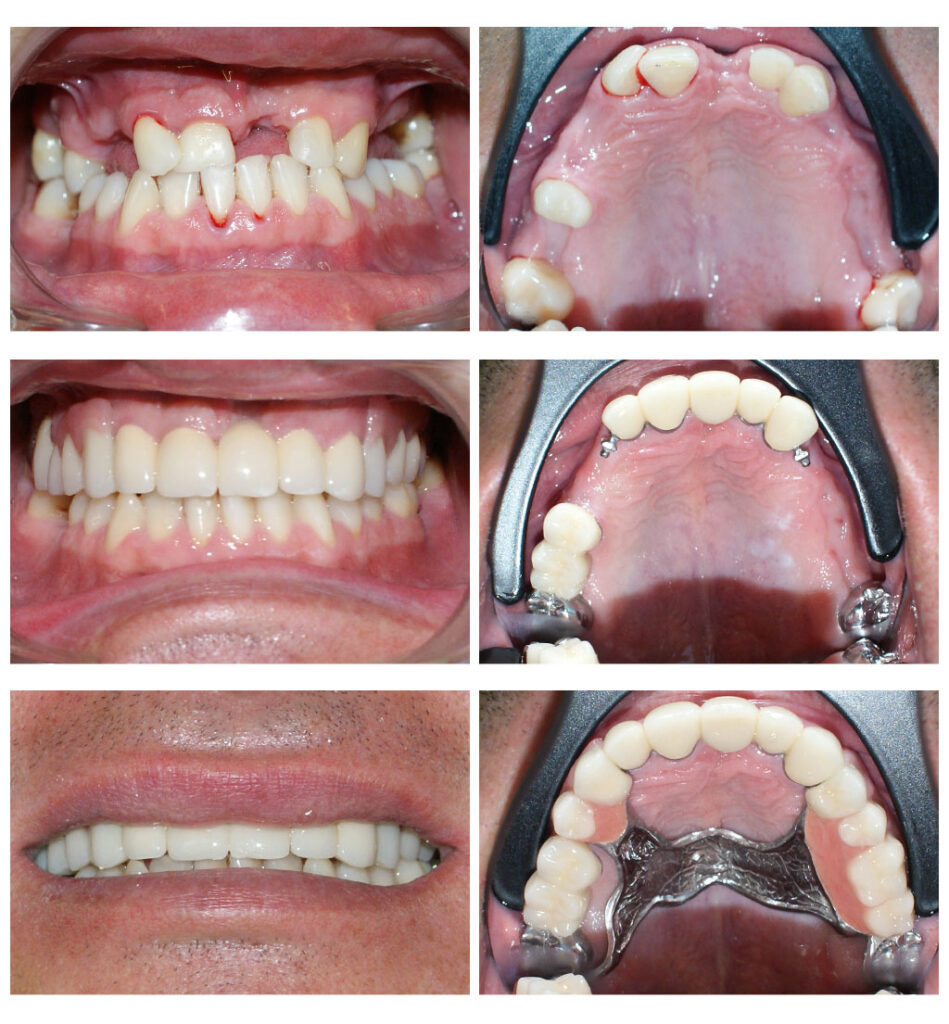

Proteza telescopată – stabilitate perfectă

Proteza telescopată  și proteză scheletată aplicate pe dinții tratați corect! Execuția riguroasă oferă stabilitate excelentă.